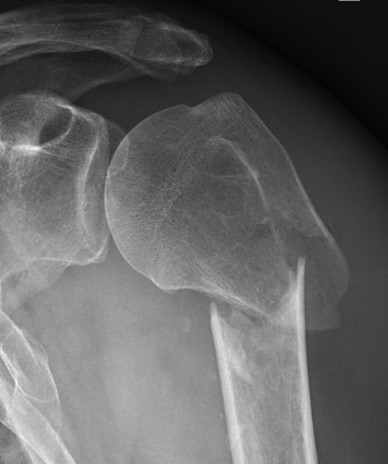

Deforming Forces

| 2 part fracture | Greater tuberosity fracture | Lesser tuberosity fracture |

|---|---|---|

|

Pectoralis major displaces shaft medially Head internally rotated by SSC |

Fragment pulled postero-superior Combination of supraspinatus / infraspinatus / Teres minor |

Displaced medially by subscapularis |